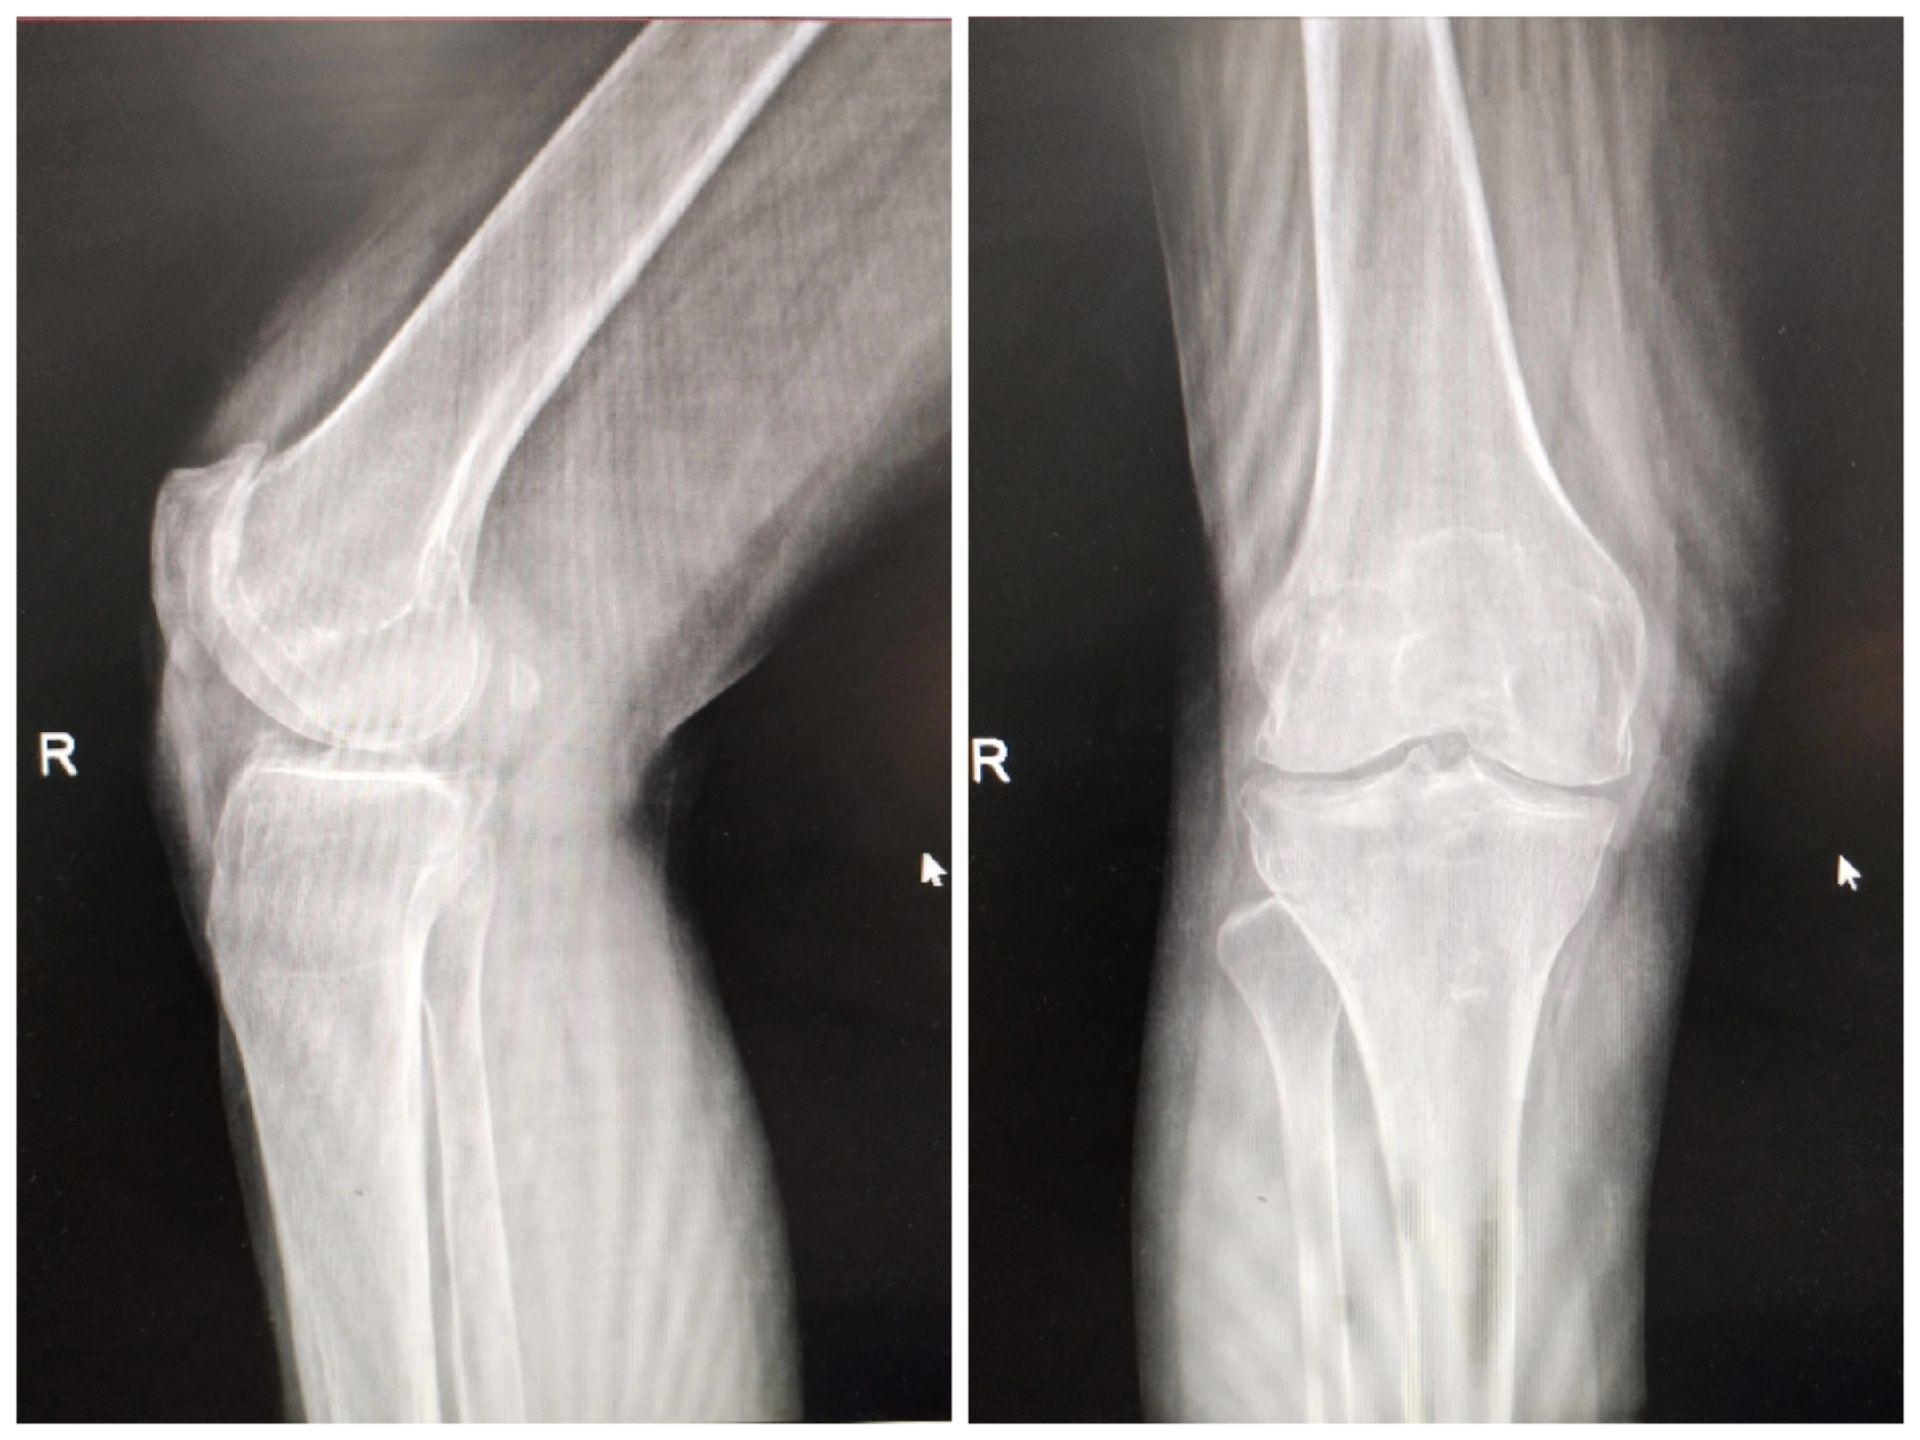

UKA单髁置换。膝关节骨关节炎,同期双侧单髁置换,术后四天出院,快速康复,省医关节外科🌹